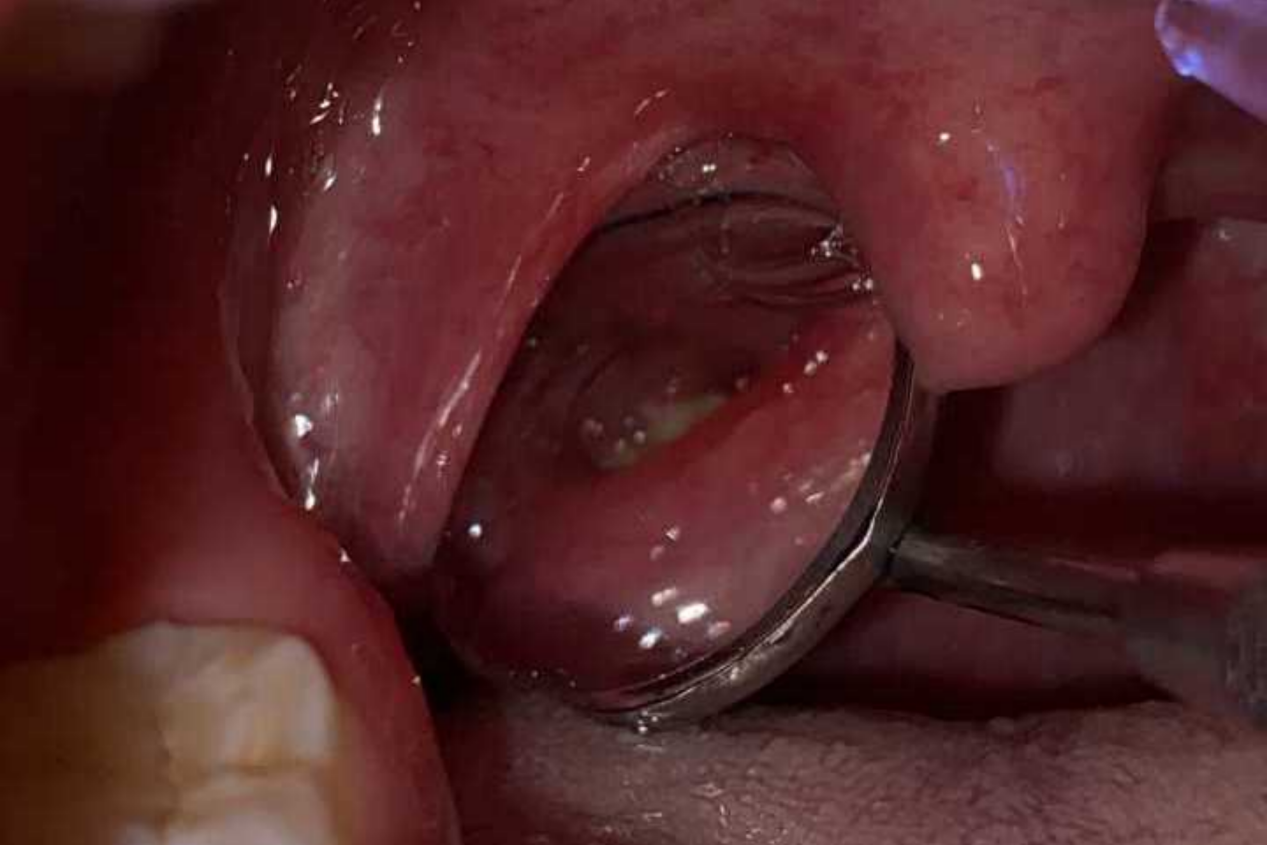

可用勺子将舌头压下,可看到扁桃体有颗粒状灰白色物质,同时伴有口臭、咽部异物等。

可用勺子等干净物体向下压住舌头,用镜子观察扁桃体处,可发现灰白色、质地较硬的细小砂石,或可以在肿大的扁桃体内触及较硬的肿块,触碰时有轻微痛感。如果并发了扁桃体炎症时,可见舌腭弓出现慢性充血、患侧舌腭弓向前隆起,扁桃体肿大,表面黏膜可由脓性渗出物。当挤压患侧扁桃体时,扁桃体隐窝口可有少量白色豆腐渣样分泌物溢出。